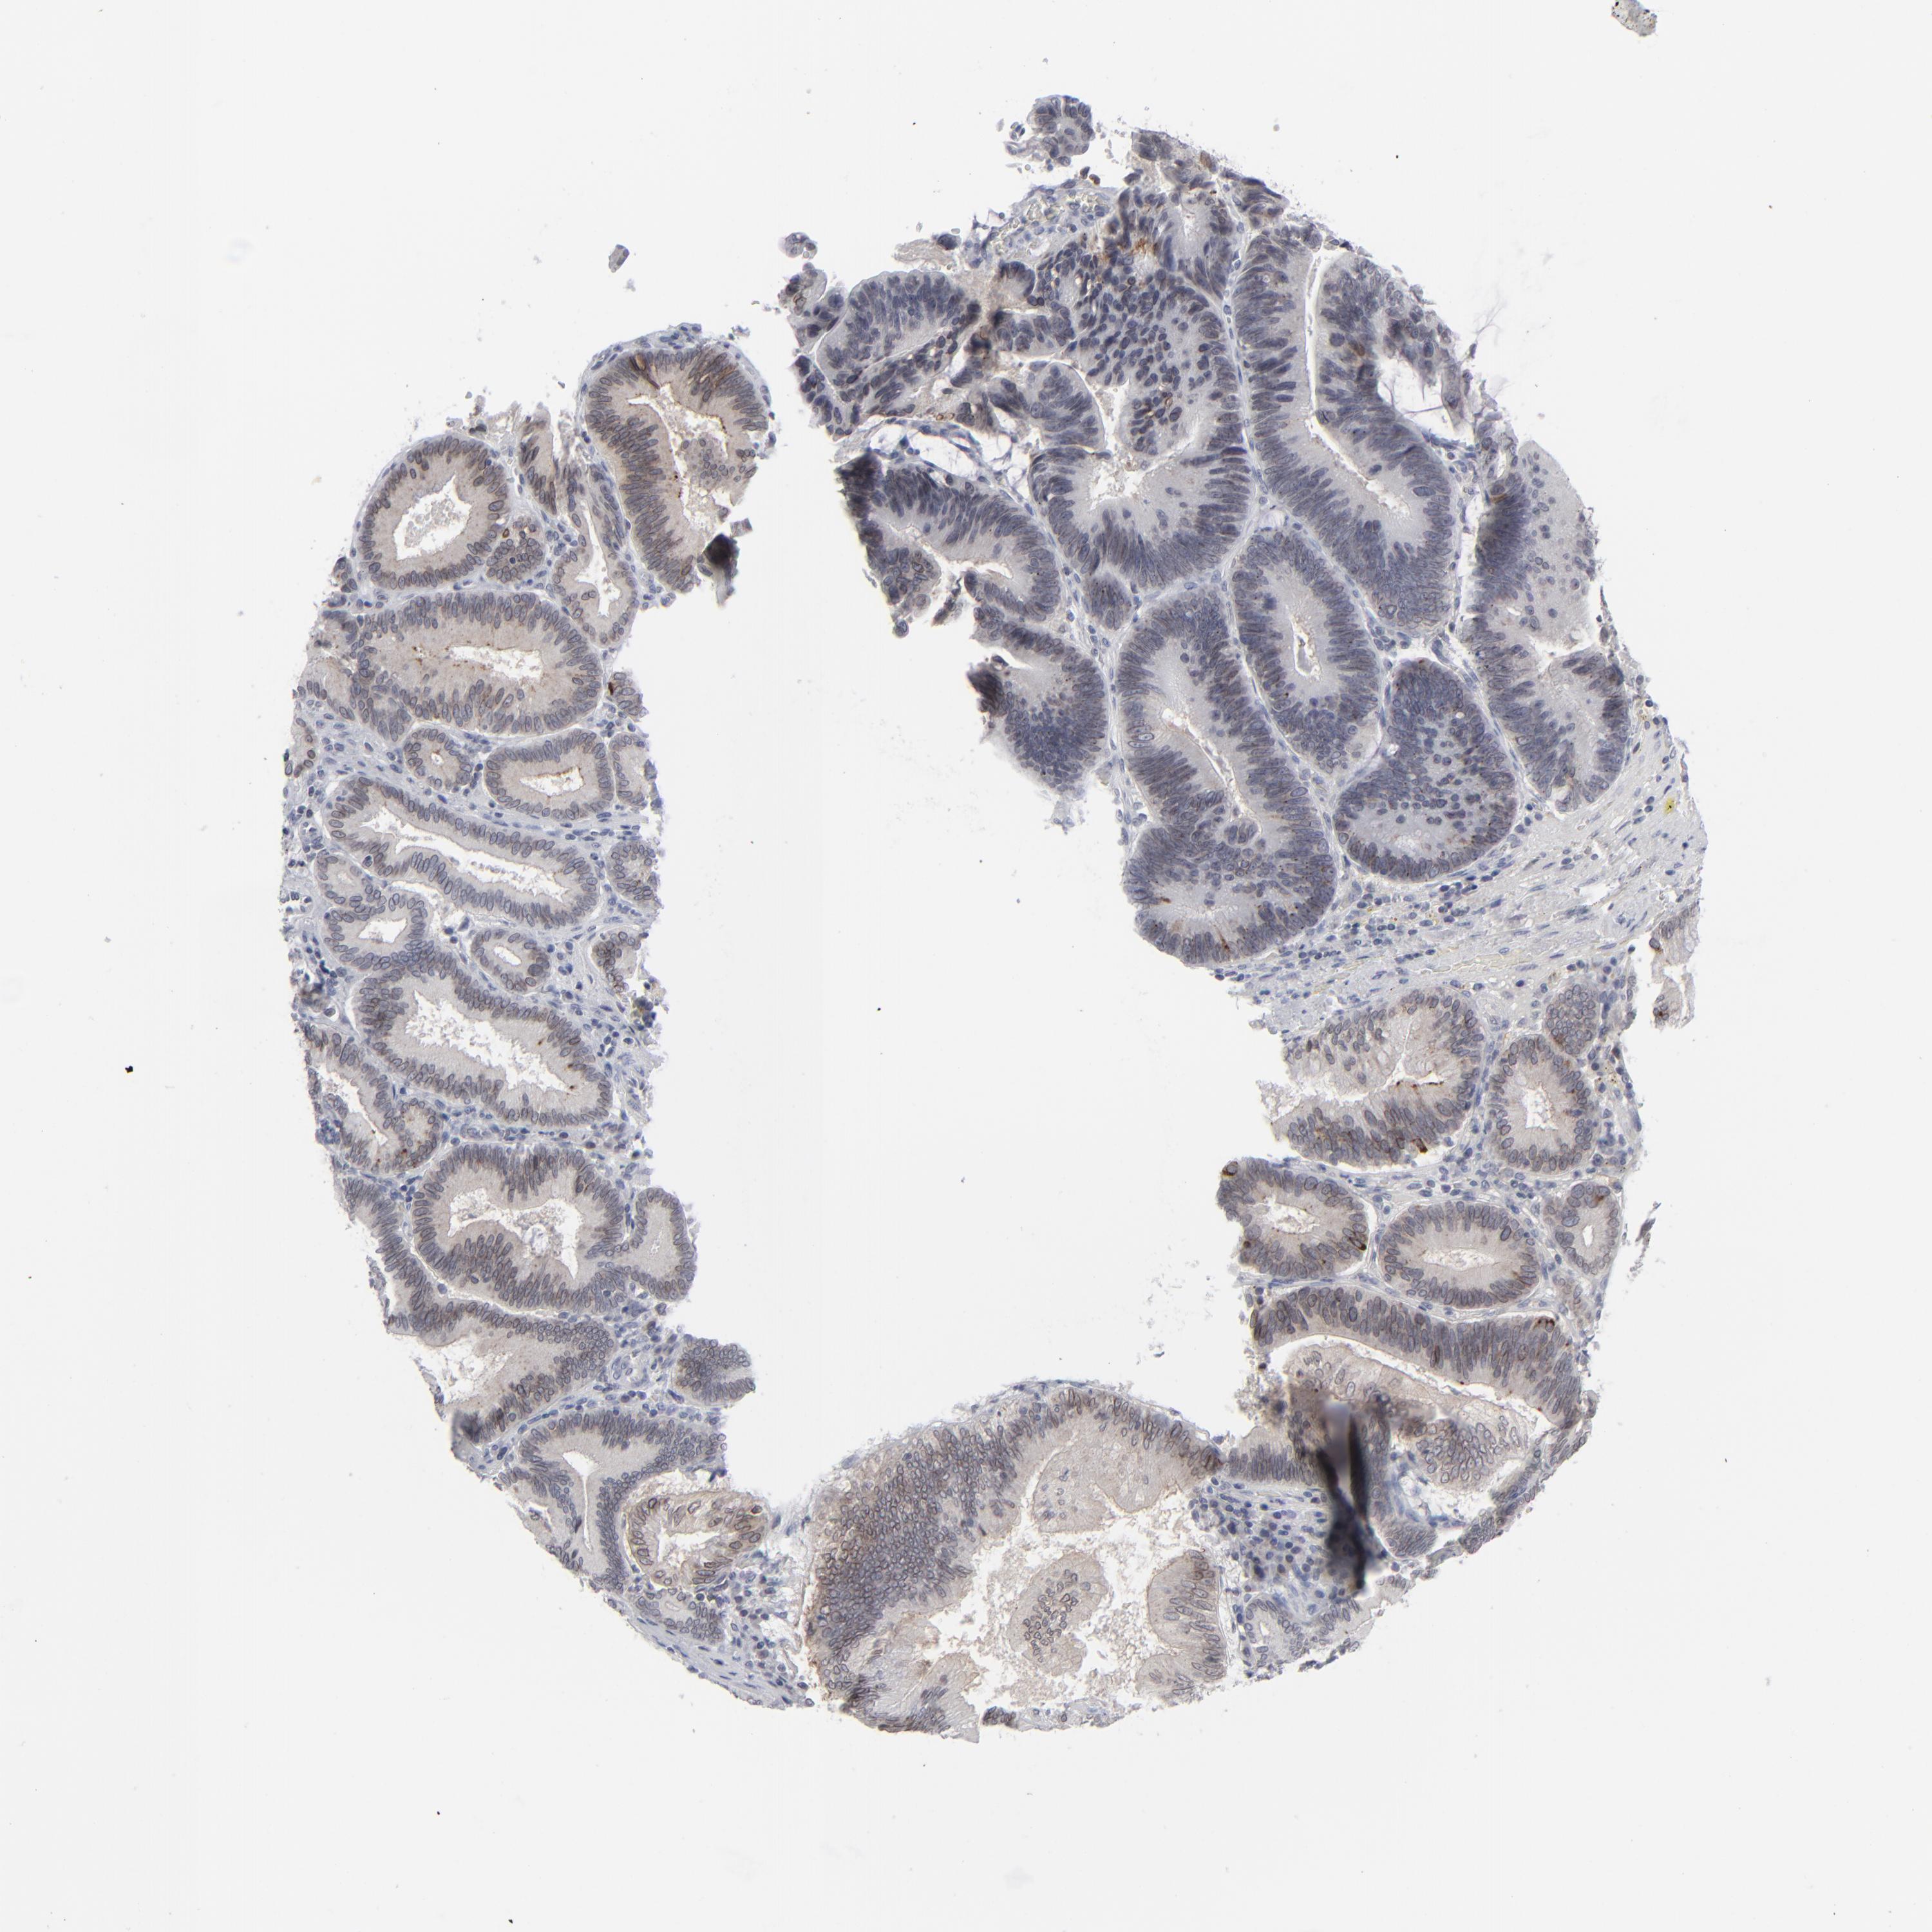

PANCREATIC CANCER - Protein expressioni

A mouse-over function shows sample information and annotation data. Click on an image to view it in a full screen mode. Samples can be filtered based on level of antibody staining by selecting one or several of the following categories: high, medium, low and not detected. The assay and annotation is described here.

Note that samples used for immunohistochemistry by the Human Protein Atlas do not correspond to samples in the TCGA dataset.

Antibody stainingi

Antibody staining in the annotated cell types in the current human tissue is reported as not detected, low, medium, or high, based on conventional immunohistochemistry profiling in selected tissues. This score is based on the combination of the staining intensity and fraction of stained cells.

Each image is clickable and will lead to virtual microscopy that enables deeper exploration of all samples and also displays staining intensity scores, fraction scores and subcellular localization as well as patient and tissue information for each sample.

Antibody HPA021816

Antibody CAB002209

Staining

High

Medium

Low

Not detected

Intensity

Strong

Moderate

Weak

Negative

Quantity

>75%

75%-25%

<25%

None

Location

Nuclear

Cytoplasmic/membranous

Cytoplasmic/membranous,nuclear

Adenocarcinoma, NOS

Adenocarcinoma, metastatic, NOS